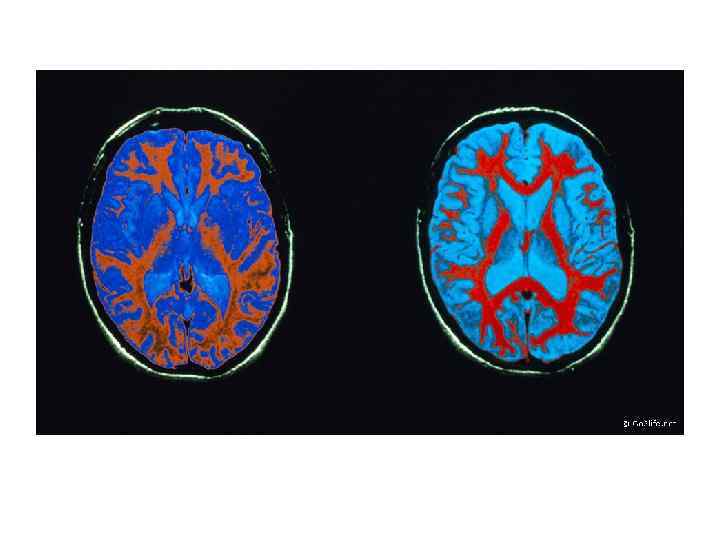

МРТ ГОЛОВНОГО МОЗГА